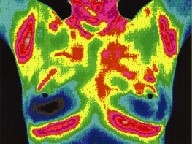

Why Breast Thermography?

Breast Thermography is an adjunctive diagnostic procedure approved by FDA for breast cancer screening.

Breast Thermography spots changes in a breast 8 to 10 years ahead of mammograms.

Breast Thermography delivers no radiation to the breast.

Breast Thermography requires no compression nor any contact with the breast to create images.